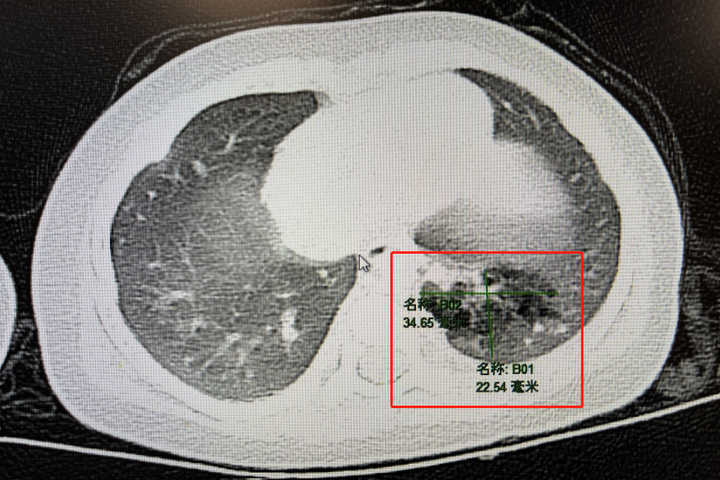

接诊的小儿胸心外科主任顾海涛教授,仔细询问了乐乐的病史并阅览胸部CT,发现肺部病变并无明显的恶性肿瘤特征,于是安排了胸部增强CT检测,通过增强扫描,发现有一支源自主动脉的异常血管穿入了左下肺病灶,最终明确诊断为“肺隔离症”,也就是我们常说的隔离肺。

乐乐的肺部CT影像,红框内为“隔离肺”